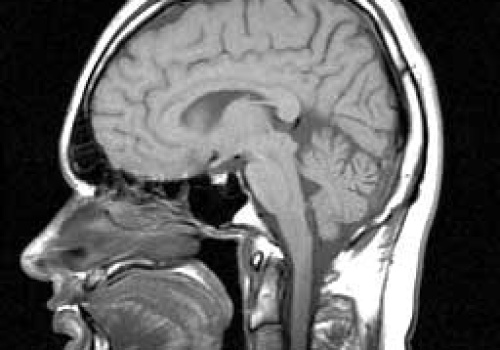

Dzisiaj przypada Światowy Dzień z Depresją. Zdrowie psychiczne przestało być wyłącznie kwestią medyczną – dziś to także realny wskaźnik, który wiele może powiedzieć o kondycji gospodarki. Jak wynika z danych Światowej Organizacji Zdrowia, każdego roku z powodu lęku i depresji na świecie traconych je...

Każdego roku z powodu lęku i depresji na świecie traconych jest 12 mld dni roboczych. To oznacza około 1 bln dolarów strat dla globalnej gospodarki – wynika z danych Światowej Organizacji Zdrowia. W Polsce depresja zbiera żniwo – choruje na nią ponad...